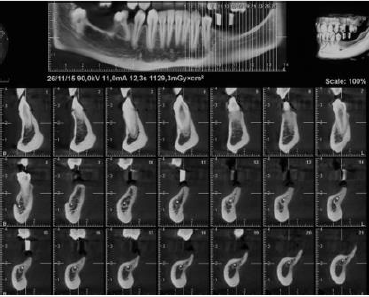

A female patient 28 years old was referred by the orthodontist to complete her dental treatment. Patient presented with several missing teeth due to agenesis, she had only two upper permanent molars and a deciduous one in the lower right side. The request of the patient was to replace two lower molars and one in the upper right side in order to restore proper occlusion (Figures 1-3). As part of the study case the patient was sent for a CBCT in order to evaluate the condition of the edentulous areas (Figure 4) [1].

Unfortunately, the 3D evaluation showed a severe type of horizontal bone resorption in both molar areas, right and left. Priority was given to the lower left side where one bicuspid and all three molars were missing. Nevertheless, the anatomy of the area showed how the combination of horizontal bone loss plus very superficial mandibular canal would allow the placement of one only implant. As part of the planning, stone casts were taken and with the aid of periodontal probes was evaluated the kind of augmentation needed (Figure 5). In order to accommodate a standard diameter implant was requested an augmentation of at least 5-6 mm. It was decided to address this area with the aid of a bone lamina (Cortical Lamina, OsteoBiol by Tecnoss, Coazze, Italy) technique associated with a mix of autogenous bone mixed with collagenated porcine bone graft (GenOs, OsteoBiol by Tecnoss, Coazze, Italy) [2].